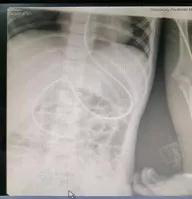

针对这一新的诊疗方案,科室营养专科护士进行了充足的前期准备,观摩成人鼻肠管盲插置入技术,查阅大量文献、资料,全面掌握了该项技术实施过程中可能存在的问题及处理对策。7月10日下午,在赵金芳护士长的指导下,营养专科护士张汝彦顺利为患儿置入了鼻肠管,并通过X线影像检查,最终确认置管成功。